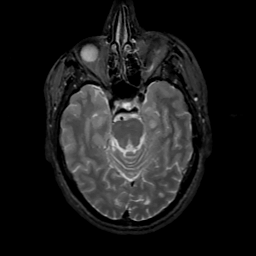

MR Study #7, March 24, 1991 -- Slice #17